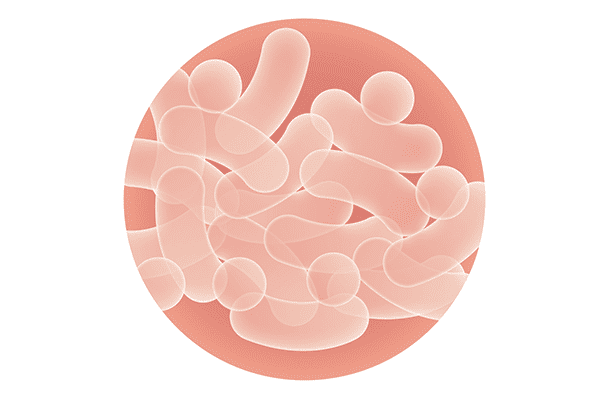

歯周病はプラーク=バイオフィルムが原因で起こる感染症です。 歯周病を予防するにはバイオフィルムのコントロールが重要になります。 バイオフィルムのコントロールには機械的なコントロール、つまりブラッシングが最も有効であることは言うまでもありません。

プロバイオティクス(probiotics)による生物的コントロール

- 健康な時、細菌は一定のバランスが取れた細菌叢を構成。

- そのバランスが崩れると、病原菌等の悪玉菌が増え、善玉菌が減る。

- プロバイオティクスは善玉菌を積極的に増やしてやることで善玉菌と悪玉菌のバランスを整え、元の正常な細菌叢に戻す働きをする。

※プロバイオティクスとは 抗生物質(antibiotics)に対比される言葉で生物問の共生関係(probiosis)を意味する生態学的用語が起源です。

プロバイオティクスは抗生物質のように有害な菌と同時に有益な菌まで殺すのではなく、元々体内にいる有益な菌を積極的に増やして体の健康を守ろうというものです。